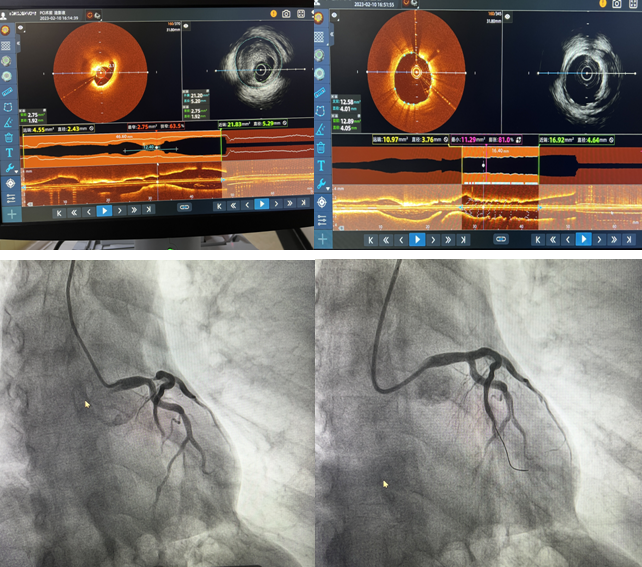

2月10日,我院心內(nèi)二科主任郭明帶領的心臟介入團隊成功完成棗莊市首例IVUS-OCT雙模一體機全程指導PCI手術,標志著我院冠脈介入技術“精準化”又向前邁進了一大步。

患者,男,71歲,因“發(fā)作性胸痛5天”住院,肌鈣蛋白陽性,胸導聯(lián)T波倒置,臨床診斷為急性冠脈綜合征。冠脈造影檢查示:左前降支開口至左主干重度狹窄達90%,并累及對角支開口狹窄達80%?;颊咦笾鞲杉扒敖抵ч_口同時存在嚴重狹窄,狹窄嚴重且存在不穩(wěn)定斑塊,需更加精準支架定位與覆蓋病變,要保證支架的貼壁絕對良好,此處一旦形成亞急性血栓極有可能引起患者猝死,單純的冠脈影像并不能完全達到此種理想的指導作用。經(jīng)過與患者家屬溝通,郭明主任和楊大成副主任組織團隊人員討論后,決定應用IVUS-OCT雙模一體機全程指導下實施病變血管介入手術。介入科李紅衛(wèi)主任及盧慶林副主任進行圖像采集及分析解讀,確定冠脈內(nèi)斑塊性質(zhì),精準判定血管直徑、病變長度和支架落腳點,指導選擇合適型號的支架,術后再次應用IVUS-OCT雙模一體機,觀察支架貼壁及膨脹良好,支架兩端無夾層,手術取得成功。

近年來如何進行優(yōu)化的介入治療成為當前心血管領域的熱點。單純冠脈造影無論在定性診斷還是定量診斷上,都存在一定的局限性。IVUS具有更深的成像深度,但空間分辨率差;OCT具有更好的分辨率,能更好地對比斑塊成分,但其成像穿透深度有限。因此,單一的IVUS或OCT很難完全提供血管及斑塊內(nèi)部完整的解剖學信息。IVUS-OCT一體機是集光學成像、聲學成像、硬件和軟件于一體的新型血管內(nèi)成像技術,實現(xiàn)了利用一根導管、一次掃描成像就可以完成兩項血管內(nèi)影像檢查,是精準PCI技術的進一步提升。